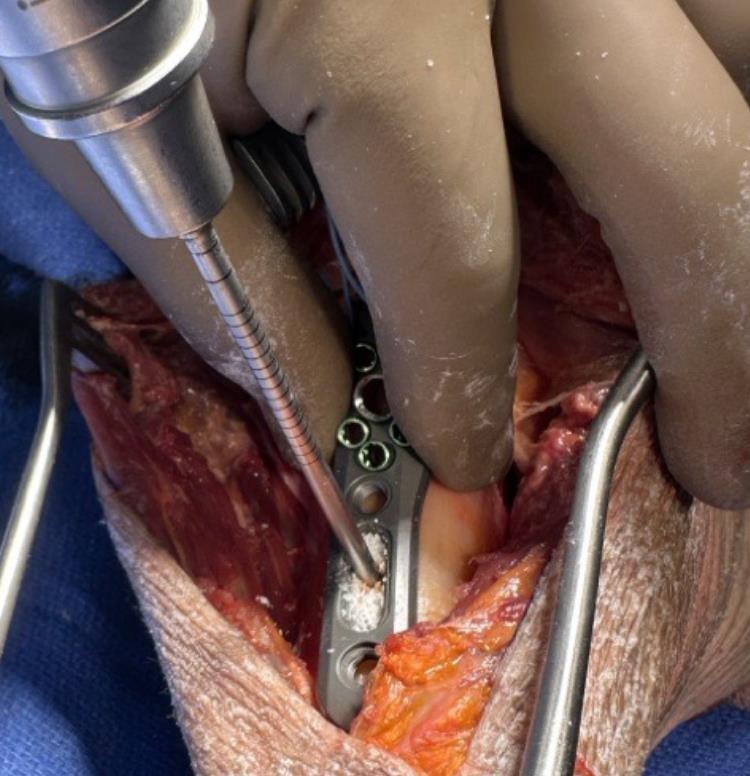

• Plating Technique

• Plate selection and positioning

• A side-specific plate (left or right) is selected, choosing straight or curved geometry and appropriate length based on the fracture pattern and need for distal fixation.

• The proximal plate is positioned 2.5–3.0 cm distal to the tip of the greater tuberosity.

• The anterior straight border of the plate is aligned just lateral to the bicipital groove, aligning the metaphyseal peg trajectories through the humeral head and maintaining space for the biceps tendon.

• If tuberosity support or anterior buttress is needed, a suture plate or buttress plate is attached to the underside of the proximal plate by engaging the V-channel and securing with a dedicated screw.

• Provisional plate fixation and central K-wire

• A 3.2 or 3.5 mm drill is used through the proximal shaft slot to prepare for a 4.5 mm FreeFix compression screw.

• The compression screw is inserted and fully tightened, providing initial plate-to-shaft fixation while still allowing some translation along the oblong slot for fine adjustment.

• A threaded K-wire guide is placed into the central post of the plate, and a 2.4 mm K-wire is drilled toward the center of the humeral head.

• Fluoroscopy in AP and lateral views is used to verify that the wire is center–center and follows the desired 135 degree trajectory.

• If the K-wire is off-center, it is removed, plate position is adjusted, and the wire is re-drilled until the central position is satisfactory.